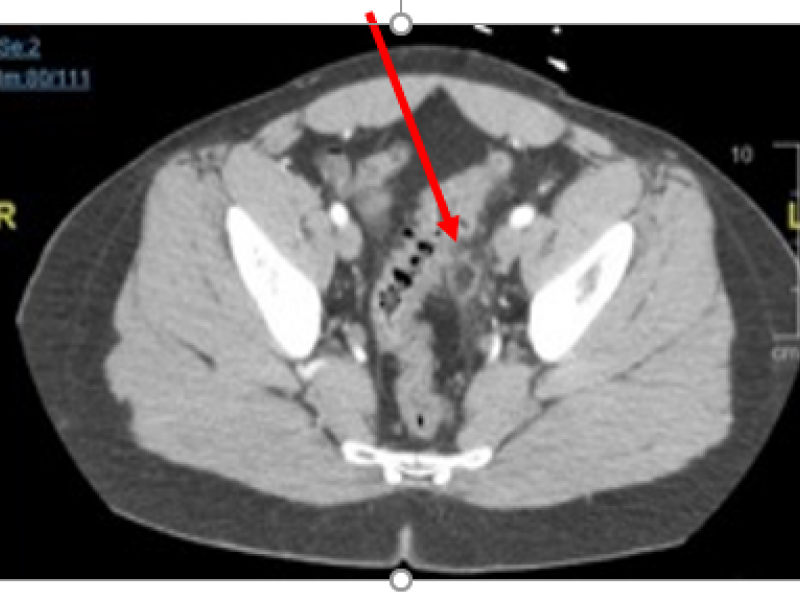

A 40 yo female presents with right flank pain. The pain is

A 42 year-old female presents with HTN, DM, and obesity 4